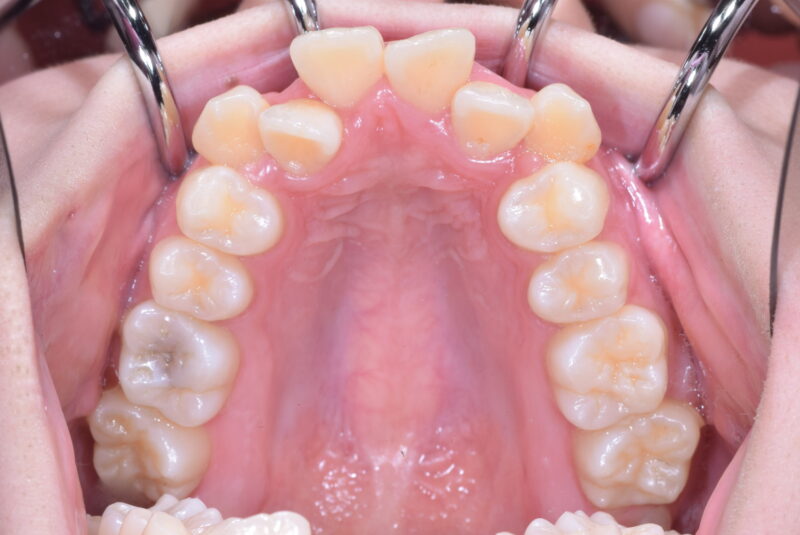

症例27 重度叢生症例

・治療前

・治療中

・治療後

①主訴 歯ならびが悪い

②診断名 前歯部叢生 Angle Cl. I

③年齢 20代女性

④治療に用いた主な装置 上顎:表側の装置 下顎:表側の装置

⑤抜歯部位 上顎:左右第一小臼歯 下顎:左右第一小臼歯

⑥治療期間 1年5か月

⑦治療費 850,000円

⑧リスク副作用 痛み・治療後の後戻り・歯根吸収・歯髄壊死・歯肉退縮などが一般的なリスクと副作用です。